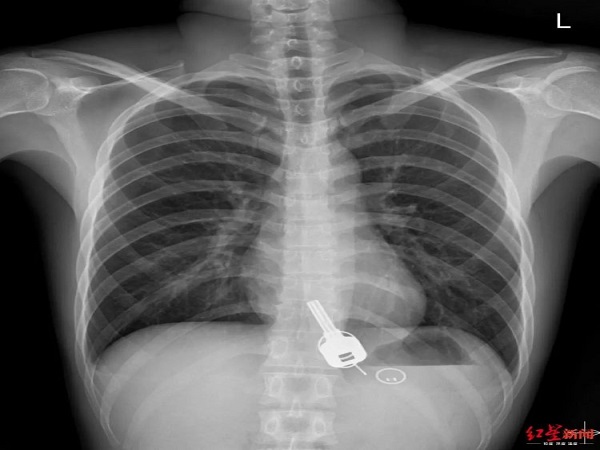

The medics were shocked to see a key lodged in Chang's oesophagus. When the medics enquired about it, he revealed that he had lost his house key the night before, but he had no explanation as to how the key ended inside his body!

It is reported that Chang was equally puzzled as the medics when he saw the X-ray as he could not remember what he did with the key as he was super drunk.

The doctors performed an immediate surgery on him as the key could not be removed through the natural process as it could tear the intestine. Even the endoscope method would rupture his oesophagus. Hence, the only option left was to surgically remove it.